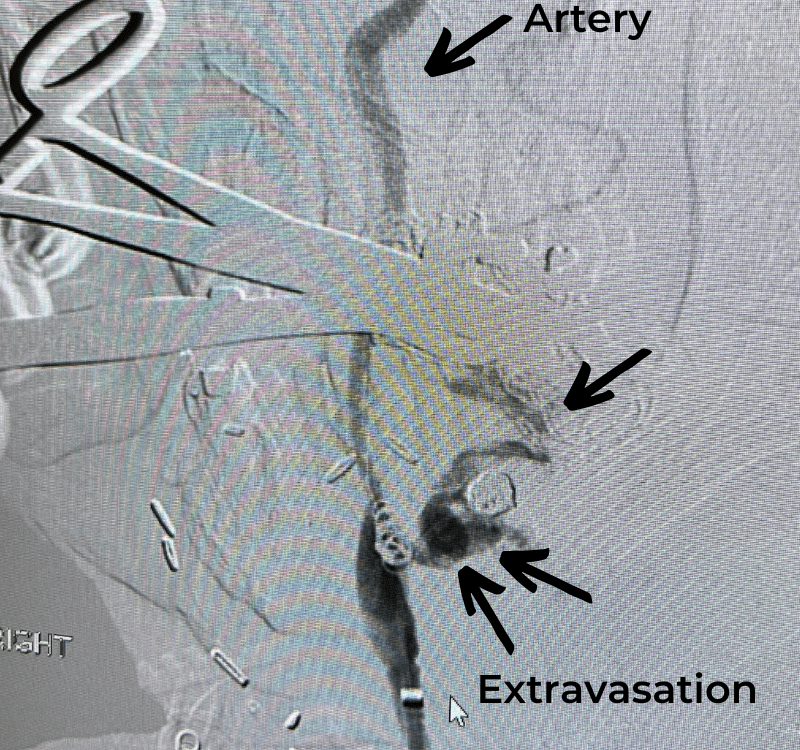

The patient is a 57-year-old woman with a long history of tonsillar cancer, treated in the past with multiple surgical procedures including right-sided mandibular surgery and […]